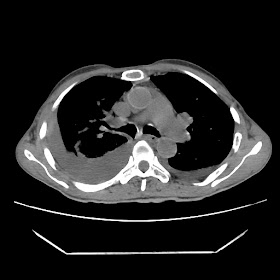

A 56 years old man with

HRCT done on summer season starting 2016